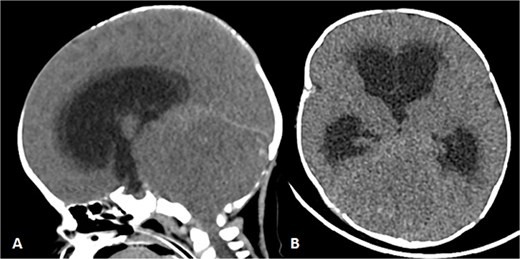

To achieve local control, surgical management using hemipelvectomy was suggested based on the lesion’s size and progression. However, this option was refused by the family. The patient was then started on chemotherapy. Whole body staging MRI did not show any metastatic lesions. After 3 months of treatment, the patient started having generalized seizure episodes. Brain neuroimaging with computed tomography (CT) scan showed an isodense mass in the posterior fossa, which was causing tonsillar herniation and obstructive active supratentorial hydrocephalus (Fig. 4). Goals of care were determined and the patient was transitioned to comfort care, after which she passed away.

Patient underwent brain CT after presenting to the ER due to seizure. (A and B) Sagittal and axial nonenhanced brain CT shows an isodense mass in the posterior cranial fossa with scattered areas of hyperdense foci denoting a hemorrhagic component that is completely effacing the fourth ventricle, causing supratentorial ventricular dilatation and periventricular hypodensity denoting cerebrospinal fluid (CSF) permeation indicating an active obstructive hydrocephalus. Also noted bilateral tonsillar herniation.